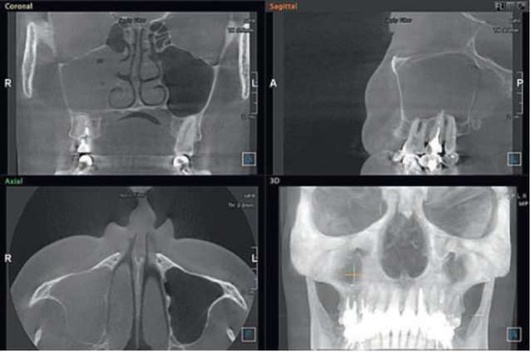

image

Рис. 5.85. Компьютерная томограмма после окончания консервативной терапии

На компьютерных томограммах диагноз «острый ВС» может выглядеть очень разнообразно, но вместе с этим всегда имеются четкие диагностические критерии - наличие одонтогенной причины (инородное тело, перфорация, признаки эндоантрального синдрома), «наличие пузырьков воздуха» и признаки обструкции естественного соустья ВС.